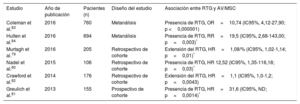

Estudios que informan del riesgo de arritmias ventriculares y muerte súbita cardiaca asociado con el realce tardío de gadolinio en pacientes con miocardiopatía dilatada

| Estudio | Año de publicación | Pacientes, n | Diseño del estudio | Localización del RTG | Asociación entre RTG y AV/MSC |

|---|---|---|---|---|---|

| Halliday et al.46 | 2017 | 399 | Prospectivo de cohorte | Pared media, subepicárdica | Presencia de RTG, HR=9,3 (IC95%, 3,9-22,3; p <0,0001)* |

| Di Marco et al.9 | 2016 | 2.948 | Metanálisis | Diversa | Presencia de RTG, OR=4,9 (IC95%, 3,3-7,3; p <0,001) Extensión del RTG, OR=3,4 (IC95%, 1,6-7,7; p <0,002) |

| Buss et al.22 | 2015 | 210 | Prospectivo de cohorte | Pared media, epicardio, difusa | Extensión del RTG, HR=1,20 (IC95%, 1,08-1,33; p <0,001)* |

| Chimura et al.44 | 2015 | 175 | Retrospectivo de cohorte | Septal/lateral subendocárdica, pared media, subepicárdica, músculo papilar | Presencia de RTG, HR=23,1 (IC95%, 2,88-184,9; p=0,003)* |

| Piers et al.45 | 2015 | 87 | Retrospectivo de cohorte | Basal, no basal | Presencia de RTG, p <0,001 (sin HR; todos los eventos en el grupo de RTG)* Extensión del RTG, HR=1,90 (IC95%, 1,35-2,67; p <0,001)* |

| Yamada et al.43 | 2014 | 57 | Retrospectivo de cohorte | Pared media, epicardio, focal, difusa | Presencia de RTG, HR=4,87 (IC95%, 1,01-23,4; p=0,048)* |

| Gulati et al.34 | 2013 | 472 | Prospectivo de cohorte | Pared media | Presencia de RTG, HR=4,61 (IC95%, 2,75-7,74; p <0,001)* Extensión del RTG, HR=1,10 (IC95%, 1,05-1,16; p <0,001)* |

| Neilan et al.41 | 2013 | 162 | Prospectivo de cohorte | Pared media, epicardio, focal, difusa | Presencia de RTG, HR=14,00 (IC95%, 4,39-45,65; p <0,0001)* Extensión del RTG, HR=1,17/% (IC95%, 1,12-1,22; p <0,0001)* |

| Nabeta et al.42 | 2013 | 75 | Retrospectivo de cohorte | ND | Extensión del RTG, HR=1,06 (IC95%, 1,02-1,10; p <0,01)* |

| Leyva et al.40 | 2012 | 97 | Prospectivo de cohorte | Pared media | Presencia de RTG, HR=16,1 (IC95%, 1,81-144,8; p=0,0128) |

| Lehrke et al.35 | 2011 | 184 | Prospectivo de cohorte | Pared media, epicardio, focal, difusa | Presencia de RTG, HR=3,37 (IC95%, 1,26-9,0; p=0,015)* |

| Assomull et al.39 | 2006 | 101 | Prospectivo de cohorte | Pared media | Presencia de RTG, HR=5,2 (IC95%, 1,0-26,9; p=0,03)* |

AV: arritmias ventriculares; HR: hazard ratio; IC95%: intervalo de confianza del 95%; MSC: muerte súbita cardiaca; ND: no disponible; OR: odds ratio; RTG: realce tardío de gadolinio.

Estudios que informan del riesgo de arritmias ventriculares y muerte súbita cardiaca asociado con el realce tardío de gadolinio en pacientes con sarcoidosis

| Estudio | Año de publicación | Pacientes (n) | Diseño del estudio | Asociación entre RTG y AV/MSC |

|---|---|---|---|---|

| Coleman et al.83 | 2016 | 760 | Metanálisis | Presencia de RTG, OR=10,74 (IC95%, 4,12-27,90; p <0,000001) |

| Hulten et al.84 | 2016 | 694 | Metanálisis | Presencia de RTG, RR=19,5 (IC95%, 2,68-143,00; p=0,003)* |

| Murtagh et al.79 | 2016 | 205 | Retrospectivo de cohorte | Extensión del RTG, HR=1,08/% (IC95%, 1,02-1,14; p=0,01)* |

| Nadel et al.80 | 2015 | 106 | Retrospectivo de cohorte | Presencia de RTG, HR 12,52 (IC95%, 1,35-116,18; p=0,03)* |

| Crawford et al.82 | 2014 | 176 | Retrospectivo de cohorte | Extensión del RTG, HR=1,1 (IC95%, 1,0-1,2; p=0,0043) |

| Greulich et al.81 | 2013 | 155 | Prospectivo de cohorte | Presencia de RTG, HR=31,6 (IC95%, ND; p=0,0014)* |

AV: arritmias ventriculares; HR: hazard ratio; IC95%: intervalo de confianza del 95%; MSC: muerte súbita cardiaca; ND: no disponible; OR: odds ratio; RR: riesgo relativo; RTG: realce tardío de gadolinio.